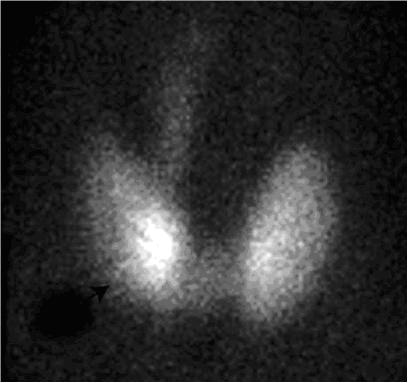

Prin detectarea la suprafaţă a radiaţiilor emise de radiotrasor, pot fi evaluate atât morfologia (dimensiuni, poziţie, forma) cât şi funcţia glandei tiroide (per ansamblu şi a eventualelor structuri nodulare). Astfel, se realizează evaluarea variantelor morfofuncţionale ale tiroidei normale: poziţia (tiroida situată retrosternală, latero-cervicală sau sublinguală), numărul lobilor tiroidieni (lob accesoriu, agenezie a unui lob tiroidian), forma glandei (ovală, de litera U sau V) şi eventualele asimetrii de captare a radiofarmaceuticului (fixare preferenţială la nivelul unui lob).

Scintigrafia tiroidiană, efectuată uzual cu Tc99m-pertechnetat, implică administrarea intravenoasă a unei cantităţi minime de radiotrasor (cu minimă iradiere), iar după circa 20 de minute de la injectare se achiziţionează o imagine a glandei tiroide (achiziţie care durează circa 5 minute).